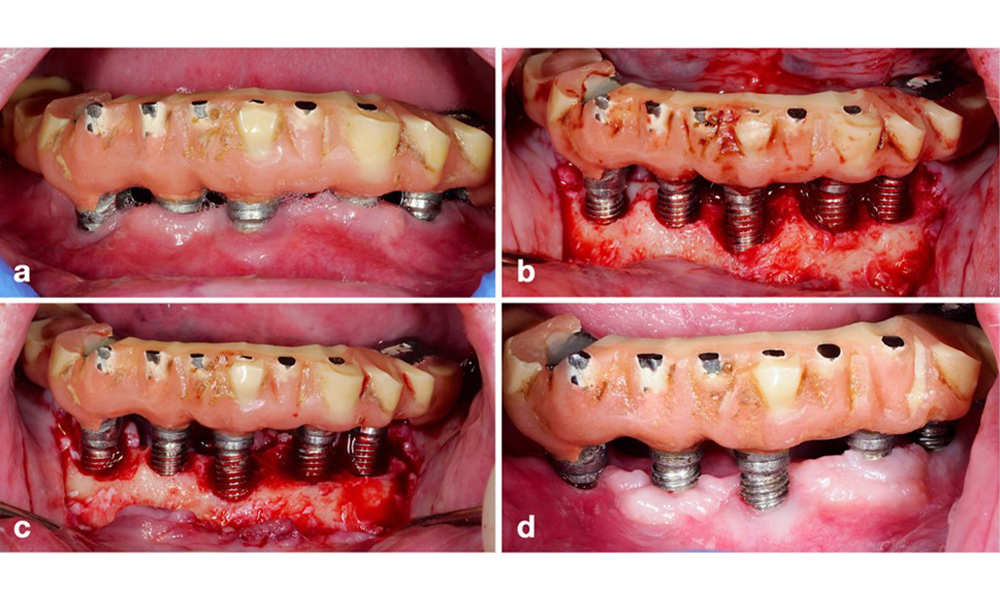

Patient, behandelt mit einem resektiven Verfahren (a). Nach Lappenelevation zeigt sich der hauptsächlich horizontale Knochenverlust (b), behandelt mittels Knochenrekonturierung (c) und apikal verschobenem Lappen. So wurde ein stabiles postoperatives Ergebnis erreicht (d).

Abb. 11. Patient, behandelt mit einem resektiven Verfahren (a). Nach Lappenelevation zeigt sich der hauptsächlich horizontale Knochenverlust (b), behandelt mittels Knochenrekonturierung (c) und apikal verschobenem Lappen. So wurde ein stabiles postoperatives Ergebnis erreicht (d).